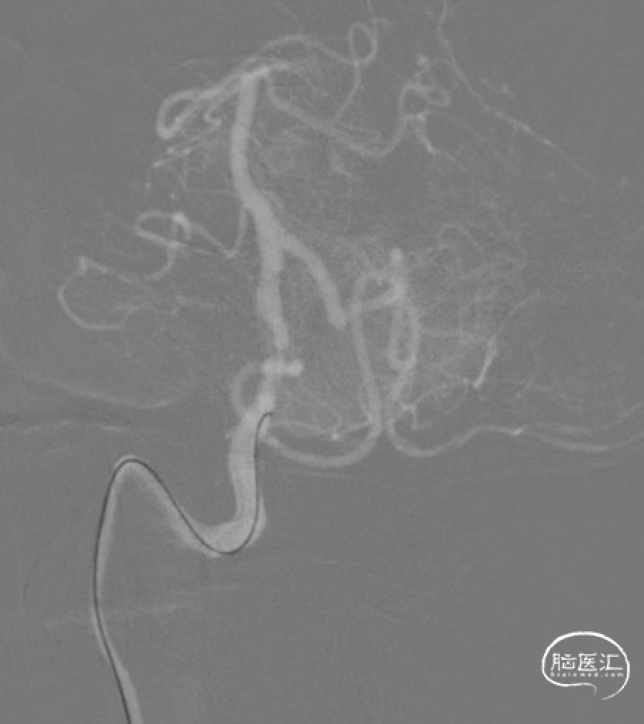

微导丝通过病变。

赛诺Neuro LPS®颅内球囊扩张导管 2.75*15mm输送至病变位置。

缓慢扩张至命名压3atm。

球扩后造影观察。